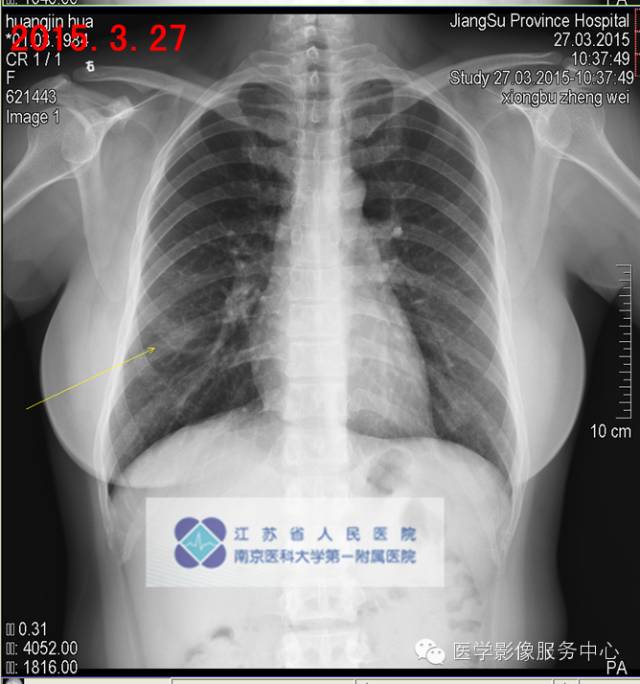

影像分析:右中肺多发病灶,较大病灶较2015-03-21片变实,感染?COP?建议穿刺活检明确病灶性质。